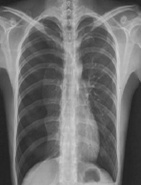

| 病史:男性,65歲,突感胸悶氣促1小時(shí)。診斷: |

| ○ 右側(cè)氣胸 | |

| ○ 右側(cè)大葉性肺炎 | |

| ○ 右側(cè)胸腔積液 | |

| ○ 肺結(jié)核 | |

| ○ 右側(cè)肺癌 |